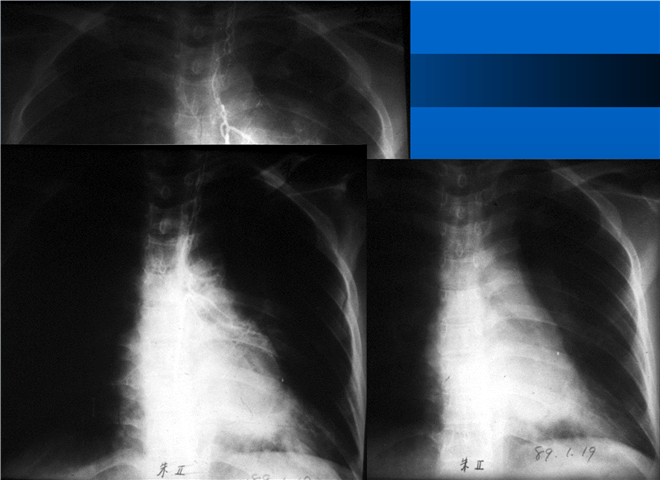

04_肺癌的介入治疗